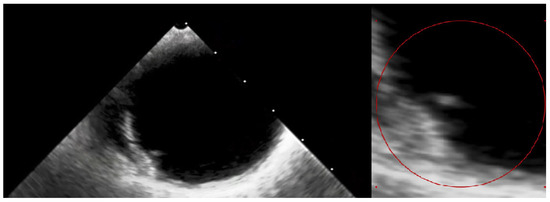

Figure 5. The transesophageal echocardiography failed to assess the aortic valve due to the artefacts. However, it confirmed the suspicion of the visible ruptured neointima within the aorta on the CT (Video S1—red circle). The patient again consulted with the Heart Team, and the decision about a conservative approach and administration of oral anticoagulation with vitamin K antagonists (VKAs) was sustained. At the 3-month follow-up, the patient was free from angina and syncope, and the control chest CT showed no sign of thrombus presence in the aortic region. The anatomical changes, such as the dimensions and shape of the aortic root, which occurred during TAVI, may have caused the dynamic switch in blood flow through the bioprosthetic valve, thus causing aortic remodelling. This contributes to the fact that the blood stagnates in the prosthetic sinuses, which complements Virchow’s triad and is attributed to thromboembolic events [7]. Furthermore, the ongoing structural bioprosthesis degeneration leading to fibrosis and calcification is often started by leaflet thickening and valve thrombosis [8]. The atherosclerotic plaque in the ascending aorta, or dissection of the neointima along the prosthesis, could also contribute to the thrombotic event. Aortic dissection was reported to be a rare TAVI procedure complication, occurring almost entirely as an acute condition. Regardless, there have been no previous reports of dissection of the neointima in the aortic prosthesis after ViV TAVI [9]. In our case, we suspect that a change in flow through the aorta or mechanical damage during the TAVI could have led to the dissection of the neointima and aortic thrombosis. Additionally, myocardial infarction in patients after TAVI can be the result of co-existing leaflet thrombosis and can cause difficulty in performing PCI procedures due to impaired coronary access [10]. In our case, the patient’s symptoms were most likely associated with the clinical presentation of ViV thrombosis and severe aortic graft thrombosis, in spite of the administration of SAPT—aspirin. The initial treatment with LMWH converted into VKA oral anticoagulants was sufficient to promote thrombus resolution and prevent recurrence at 3-month follow-up.